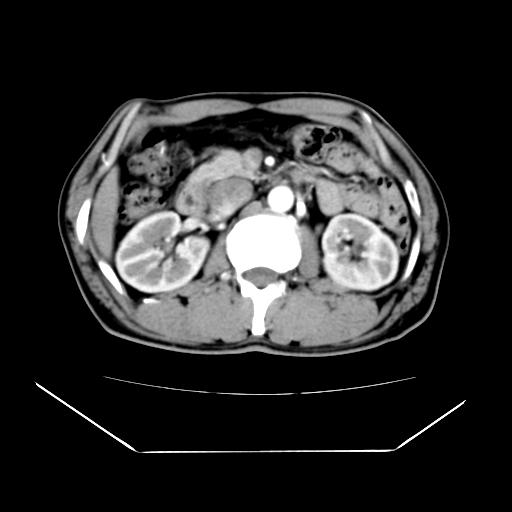

男性,55岁,外院体检afp明显升高,但b超未发现异常,否认乙肝病史。来我院ct增强。有延时扫描。

肝脏右叶动脉期可见低密度影,至延迟期被充填,考虑血管瘤可能性大。

肝右叶病灶

不排除肝右叶肝癌可能。

如果这个是癌灶的话则下腔静脉有瘤栓可能

肝6段血管瘤

血管瘤可能性大。

考虑肝右静脉影。